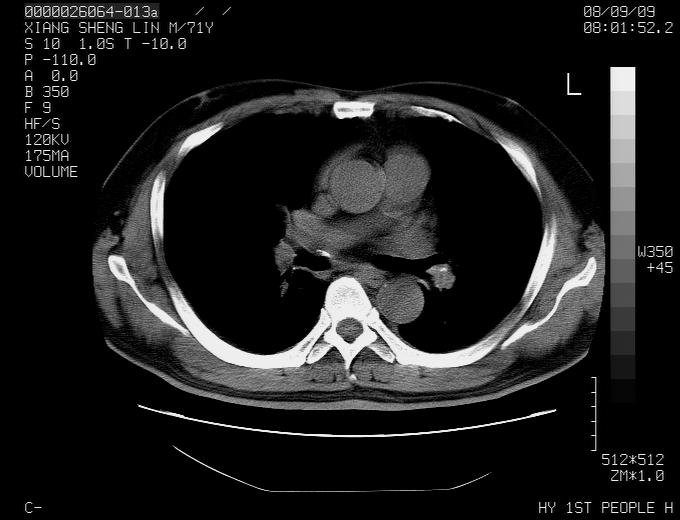

标题: CT15869:男性,71岁,因咳嗽而就诊,请讨论右上肺病变性质 [打印本页]

标题: CT15869:男性,71岁,因咳嗽而就诊,请讨论右上肺病变性质

患者,男性,71岁,因咳嗽而就诊,

典型的右肺中心性肺癌并纵隔淋巴结转移

考虑右肺中心性肺癌并右肺门及纵隔淋巴结转移。

1,右肺中心型ca,气管隆突旁淋巴结转移。

2,右膈明显抬高,建议肝脏扫描排除转移或原发灶。